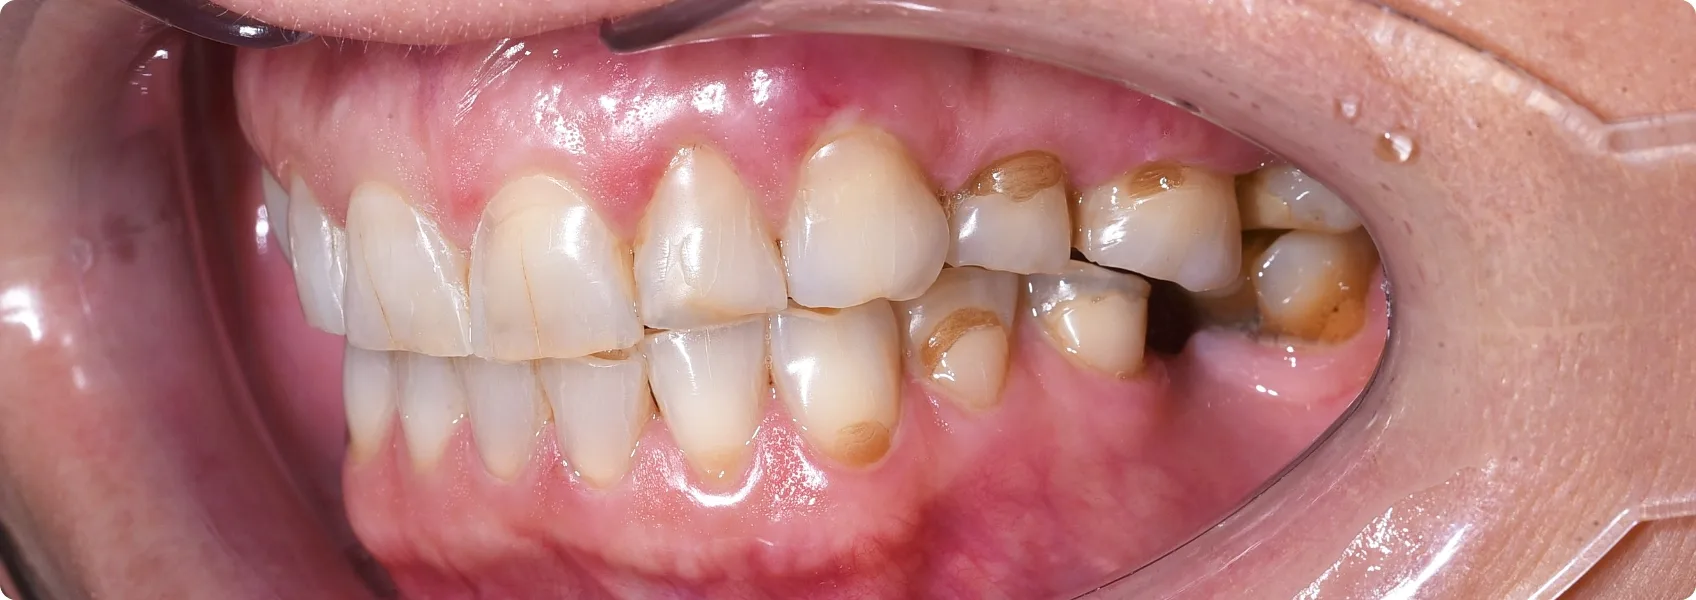

Wstępna diagnoza wykazała mocno starte, dysfunkcyjne zęby.

Dotychczasowe ustawienie zębów nie spełniało swojej funkcji. Pacjentka przez lata ścierała ich końcówki o siebie. Na powierzchni zębów pojawiały się pęknięcia i ubytki.

Pacjentka skarżyła się na obszerną nadwrażliwość.

Kiedy szkliwo — twarda, zewnętrzna warstwa ochronna zębów — ściera się, odsłania się zębina, czyli warstwa zęba ukryta pod szkliwem. W zębinie znajdują się tysiące mikroskopijnych kanalików, które prowadzą aż do nerwu zęba.

Gdy zimno, ciepło, słodkie lub kwaśne dostanie się do tych kanalików – nagły impuls bólowy trafia wprost do nerwu. To właśnie nadwrażliwość – szybka, ostra i bolesna reakcja na bodźce.

Zaczęliśmy od diagnostyki. Zdjęcia RTG pozwoliły ocenić stan korzeni zębów i kości.

Starty ząb często ma odsłoniętą lub podrażnioną miazgę zębową. RTG pokazuje, czy nastąpiło już zapalenie miazgi, martwica lub inne zmiany wymagające leczenia kanałowego (endodoncji) przed leczeniem protetycznym. Na szczęście, w tym przypadku mogliśmy przystąpić od razu do protetyki.

Na górze korony pełnoceramiczne, na dole jeszcze “tymczasówka”.

Finalnie doktor Ewa w łuku górnym założyła przygotowane korony pełnoceramiczne.

W łuku dolnym na zdjęciach widoczna jest jeszcze rekonstrukcja w formie tymczasowej – długoczasowej. Taka “tymczasówka” nie jest na stałe. Nie wygląda zbyt naturalnie, a po kilku miesiącach zaczyna przebarwiać się wskutek wnikania w materiał barwników z jedzenia. Można ją jednak nosić w oczekiwaniu na dalsze etapy leczenia.